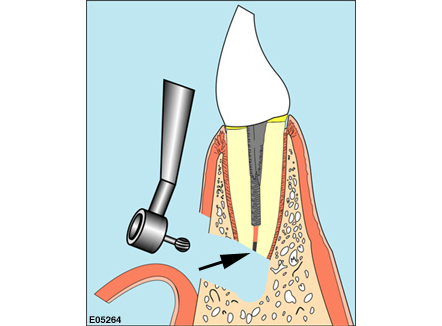

歯根端切除術とは、精密根管治療における外科的処置(歯内療法外科)の一つです。根管治療終了後に、一定の期間経過観察を行っても治癒の傾向が見られない場合に、続きの処置として、歯内療法外科を適応するケースがあります。

歯根端切除術などの歯内療法外科は、根尖と病変を摘出することで、予後不良の根尖性歯周炎を治癒させ、歯を抜かずにする治療です。

歯根端切除術の流れ

Flow01

検査・診断

レントゲン検査を行い治療ができるかを診断します。どの歯根のどの場所にどんな原因があるのかを見極めることが重要です。

治療方針として根管治療、歯根端切除術、再植術、抜歯の選択判断も重要となります。手術法、リスク、経過などの説明をして治療日を予約します。 -

Flow02

治療(外科手術)

局所麻酔で歯根端切除術(嚢胞摘出、根尖切除、逆根管充填)をします。治療は約1時間~1時間30分。翌日に術後症状のチェックと洗浄。7日後に抜糸、遠地の方は紹介状を書きますので、地元歯科で抜糸をしてもらいます。